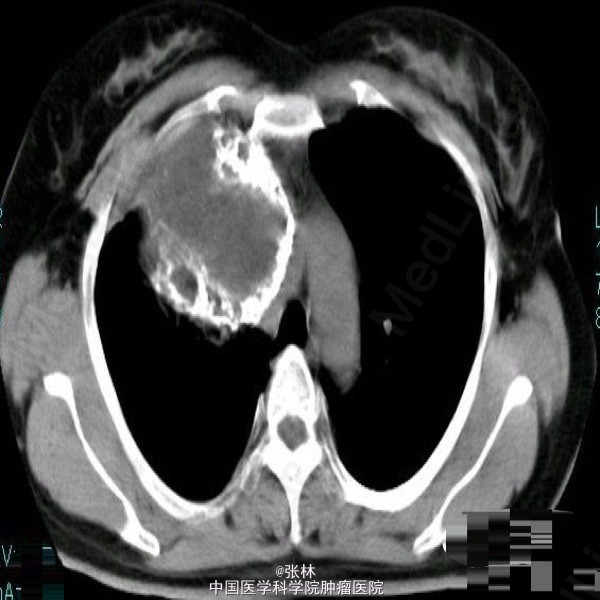

【临床病史】:患者,女性,37岁,运动后心慌、胸闷三年。右胸部呼吸音消失。叩诊呈实音。X线:右侧胸腔占位。 【影像表现】:右侧胸腔巨大囊性低密度影,大小约为109mmx118mm,边界清晰,边缘可见蛋壳样钙化,密度不均匀,CT值-35-420HU。 【影像诊断】:纵隔畸胎瘤 【最后诊断】:病理诊断:前纵隔囊性成熟性畸胎瘤。 【讨论】:畸胎类肿瘤分为囊性和实性两类,囊性畸胎瘤即皮样囊肿,多发生在前纵隔,CT为诊断该肿瘤最佳的影像学方法,可很好地显示肿块内的钙化、骨骼及脂肪成分。